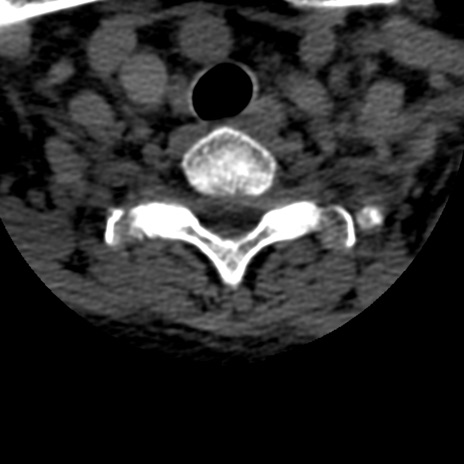

症例50 頚椎CT(横断像)

頚椎CT